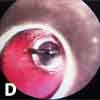

Inspiratory (A), expiratory (B), and lateral (C) chest radiographs confirmed the diagnosis of an endobronchial foreign body. Bronchoscopy revealed a blue pushpin obstructing the right bronchus intermedius and facing proximally into the large airways (D). The larynx, trachea, carina, and left main bronchus were not affected.

The pin was grasped with optical peanut-grabber forceps, it was dropped in the oropharynx and retrieved with McGill forceps and then removed with the bronchoscope. Repeated bronchoscopy showed a completely normal airway without scratches, abrasions, or punctures. The patient recovered well and was discharged later that day.